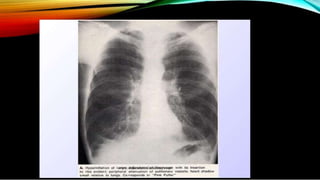

Chest radiography can be a valuable tool in the evaluation of the patient with

pneumonia. The radiologic presentation is dependent on the infectious etiology and the

underlying medical condition of the patient.

A pattern of lobar consolidation is seen most commonly in cases of pneumococcal

pneumonia. The lower lobes and right middle lobe are most commonly involved.

A pattern of patchy nonhomogenous infiltrates, pleural effusion, and cavitary lesions

are common with staphylococcal pneumonia.

Klebsiella pneumonia typically involves multiple lobes and can also be associated with

effusion and cavitation.

Viral or atypical organisms usually present with an interstitial infiltrative pattern or

patchy segmental infiltrates.

Organisms such as Nocardia, Mycobacterium, and fungi often cause nodular or cavitary

lesions, which are demonstrable on chest radiography.